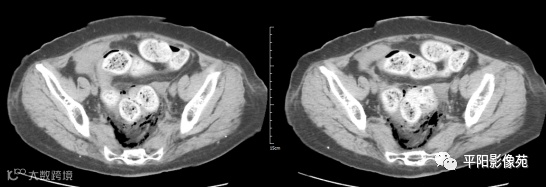

影像表现:乙状结肠前方可见不规则条状软组织密度影,边界不清,内见点状高密度;乙状结肠周围及骶前可见多发气体密度影。

影像表现:主要特点是腹腔内游离气体,可见肠壁增厚,边缘模糊,周围脂肪间隙模糊不清,并见不规则片状低密度,有粪石漏出时可见结节状高密度。